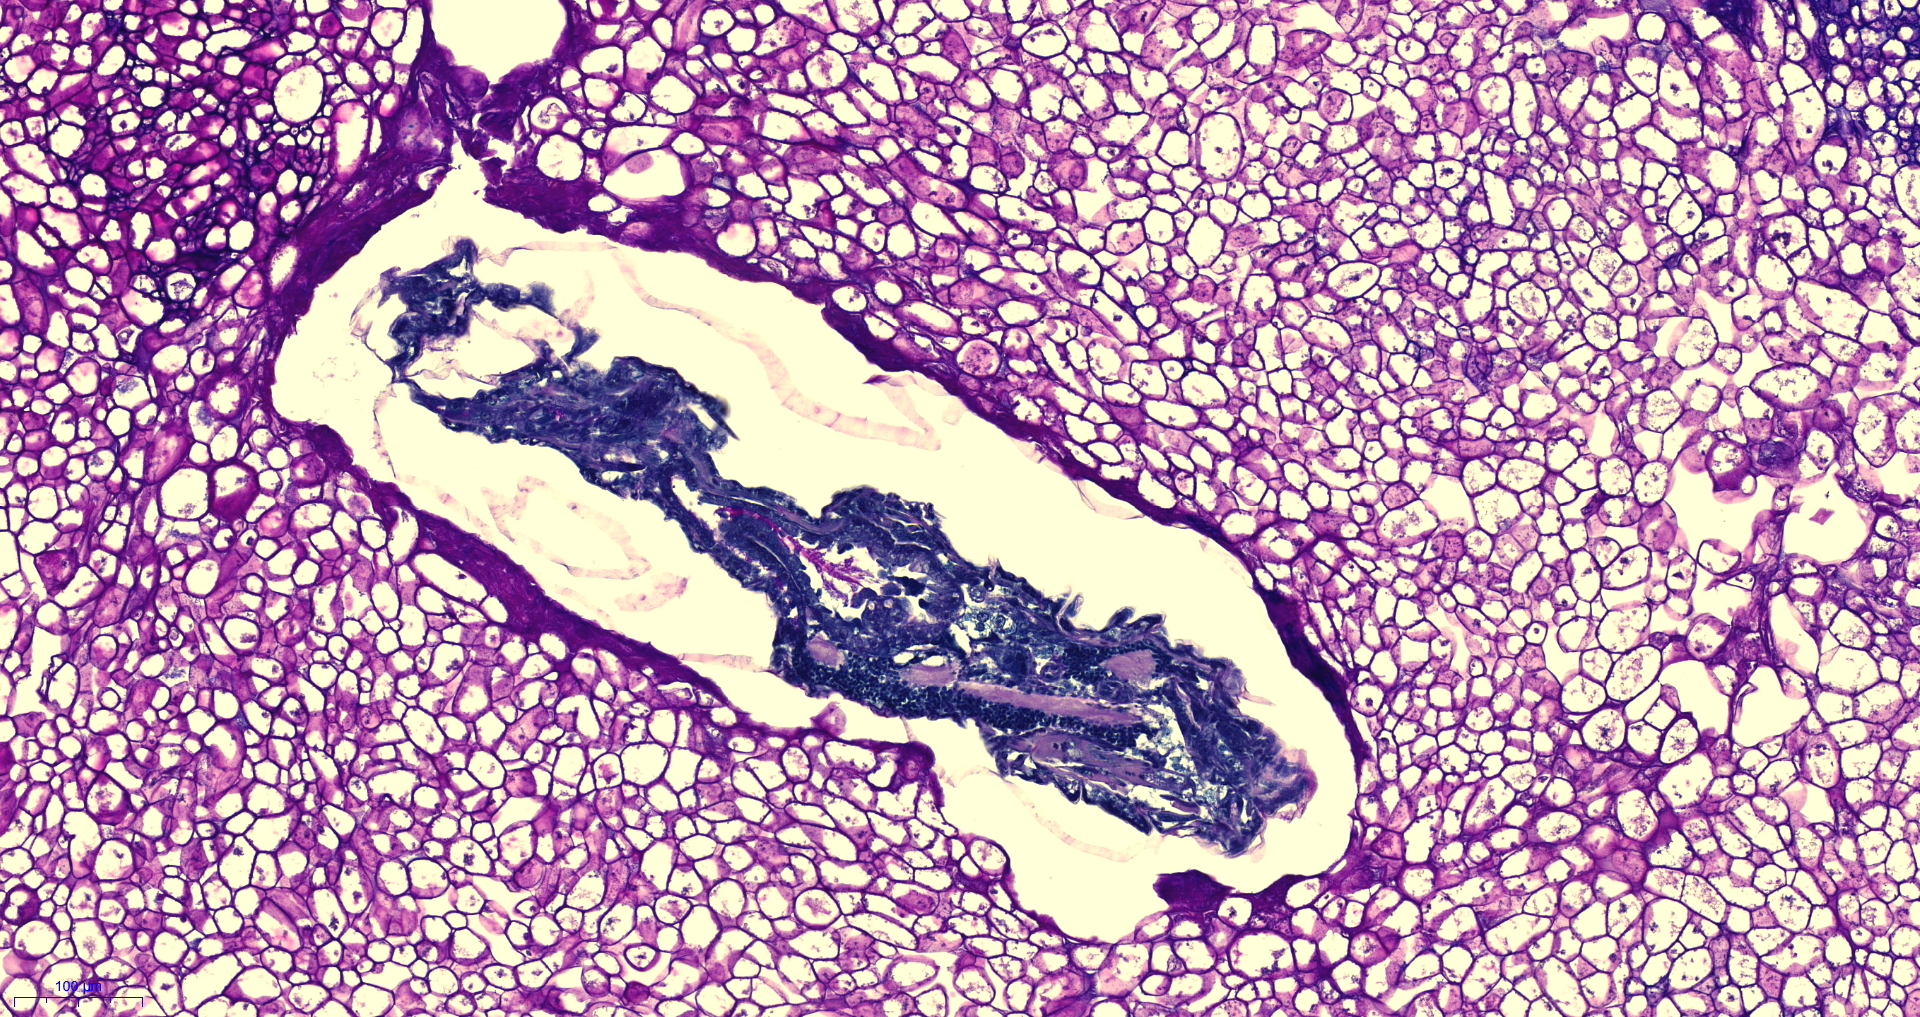

Das Material liegt mich seit knapp 2h vor und ich komme damit einfach nicht wirklich voran. Denn nicht nur das mir die passende Literatur dafür fehlt, viel schlimmer noch… Ich finde in keinem einzigen Präparat auch nur eine Spur von Sporen.

Morgen früh werde ich eine dünne Scheibe bei uns im Labor histologisch aufarbeiten… damit wir eine lichtdurchlässige Gesamtsicht erhalten ca. 1-3µm dick.